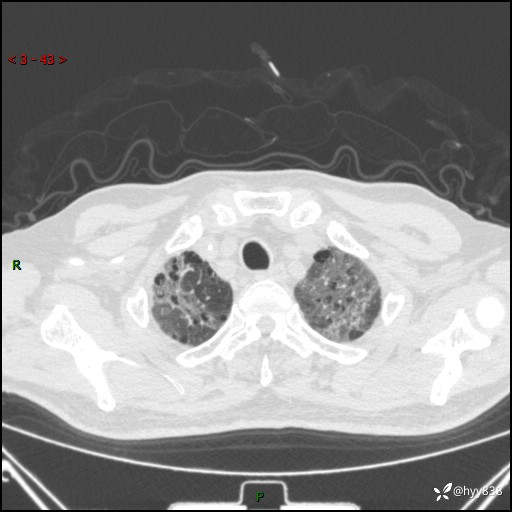

患者性别:男

患者年龄:64岁

简要病史:肝内胆管癌综合治疗后2周余,咳嗽、发热,咳白色泡沫痰。

辅助检查:CT

临床诊断:感染?

讨论:病变性质?